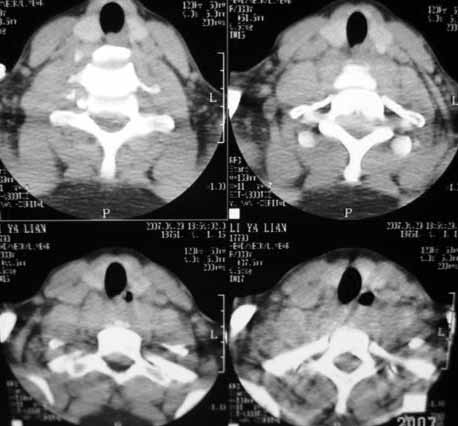

以下是引用gaoxiao在2007-4-29 21:40:00的发言:[br]颈6椎体外伤性滑脱伴附件骨骨折,建议mri进一步检查,看一下脊髓情况脊髓是否横断,病人很重。

以下是引用zhangzhongshou在2007-4-29 22:53:00的发言:[br]1、c5半脱位,i度前滑脱。[br]2、c5椎板骨折。[br]3、第7幅图像显示右侧椎板骨折,哪一节颈椎,楼主自己知道。[br]4、c2、3附件融合畸形。[br]5、考虑环椎后桥,亦为正常变异。